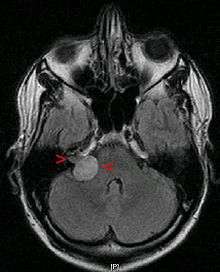

Advances in scanning and testing have made possible the identification of small acoustic neuromas (those still confined to the internal auditory canal). Magnetic resonance imaging (MRI) using Gadolinium as an enhancing contrast material is the preferred diagnostic test for identifying acoustic neuromas. The image formed clearly defines an acoustic neuroma if it is present and this technique can identify tumors measuring down to 5 millimeters in diameter (the scan spacing).

When an MRI is not available or cannot be performed, a computerized tomography scan (CT scan) with contrast is suggested for patients in whom an acoustic neuroma is suspected. The combination of CT scan and audiogram approach the reliability of MRI in making the diagnosis of acoustic neuroma.[8]

As intracanalicular tumors grow, they tend to expand into the cerebellopontine angle (CPA), leading to their characteristic "ice-cream-cone like" appearance on a radiograph. When the tumor expands extracanalicularly, the growth rate often increases, since it is no longer confined by the bony auditory canal. As the schwannoma expands into the CPA, it may infringe on cranial nerve V (controls facial sensation, chewing and swallowing) and cranial nerve VII (controls facial expression and taste). Cranial nerve VIII, along with these two nerves, also passes through the CPA, so more serious or complete hearing loss and episodes of vertigo may occur as the tumor infringes on it there.